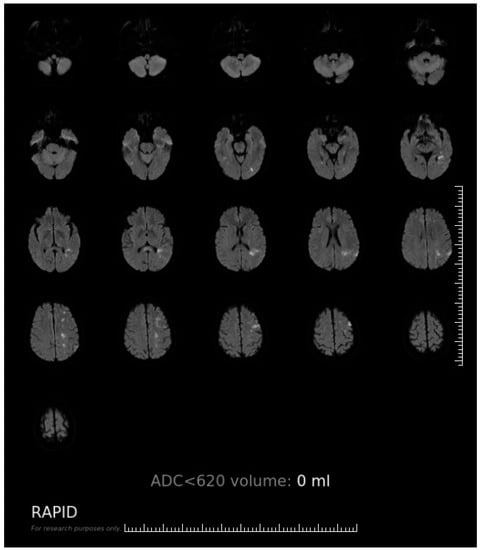

Appendix A. The Software Interface and Evaluating Procedure